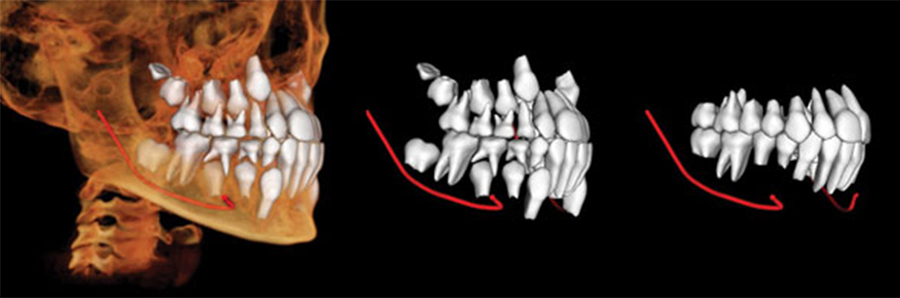

Future Smiles Orthodontics is proud to announce Guam’s first i-CAT CBCT imaging machine. This state-of-the-art technology and software are provided by i-CAT and Anatomage, the world leaders in 3D imaging for orthodontics. They have recently announced tech support for the western Pacific, and Dr. Paul is happy to announce that this will be incorporated into his services. Not only is this technology top of the line, it leads the pack on diagnosing and screening for potential tooth impactions, jaw irregularities, and sleep apnea. Patients love it because it looks like an awesome video game, but also because it more clearly diagnoses their problem areas and makes treatment even faster!